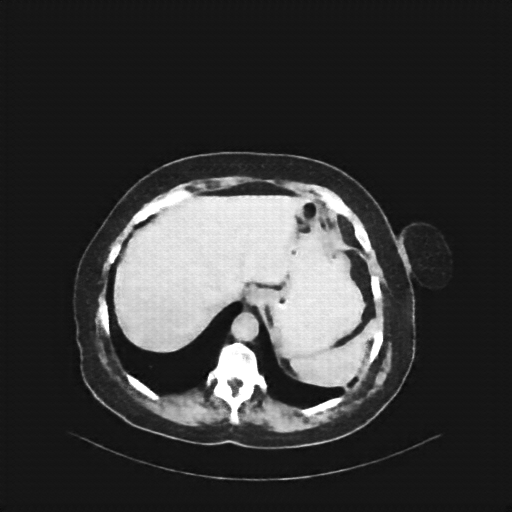

Original VENOUS CT scan

Full window (WL 1023.5, WW 4095 β Low β1024, High +3071)

Actual HU range: [-160.0, 240.0]

Lung window (WL -600, WW 1500 β Low β1350, High +150)

Actual HU range: [-160.0, 150.0]

Mediastinum window (WL 40, WW 400 β Low β160, High +240)